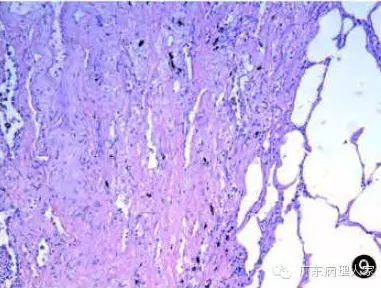

间质性肺炎镜下

间质性肺炎镜下,间质性肺炎肺纤维化

间质性肺炎病理切片